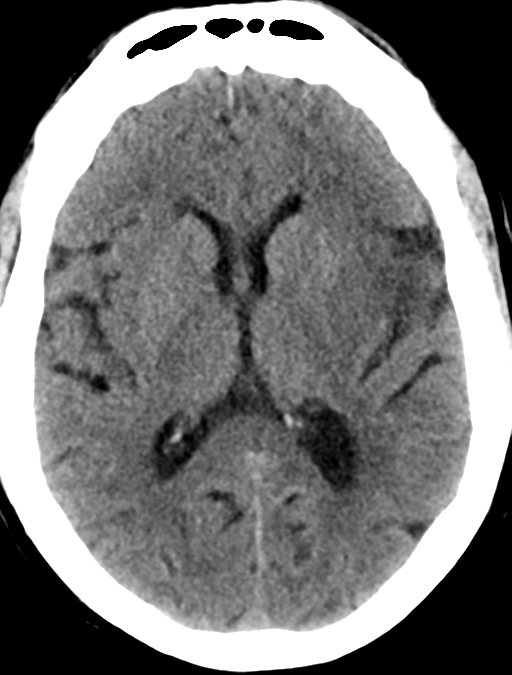

• Xuất huyết trong nhu mô não tự phát không do chấn thương (Spontaneous Nontraumatic Intracranial Hemorrhage - pICH)